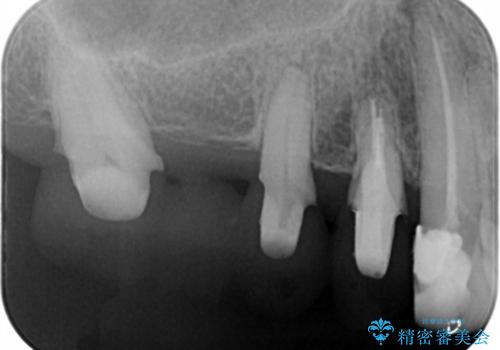

- 数十年前、アメリカで行った治療部位のやり直しを希望されてご来院。

ツギハギの修復が行われてきた被せ物は、縁が合っておらず隙間があり見た目も悪くなってしまっていました。

古い被せ物を除去し、中の状態をキレイにしたうえで改めて金属を使用していない被せ物で噛み合わせの回復を行いました。